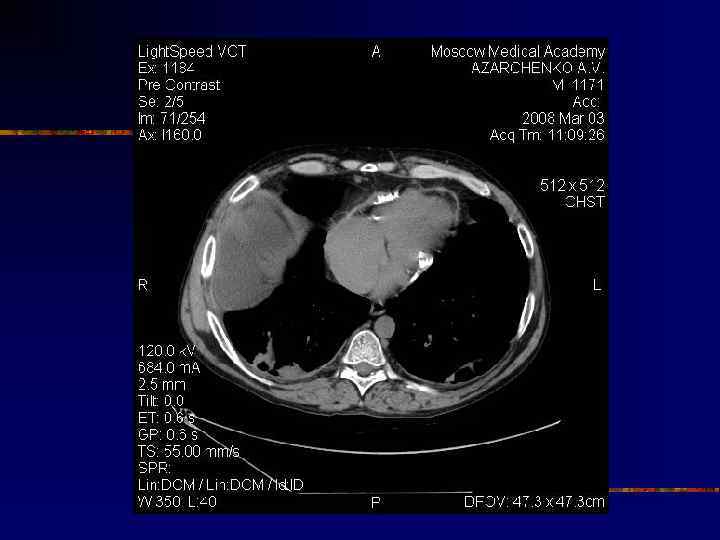

Кальциноз перикарда

Перикардэктомия: негативные предикторы n n n III и IV ФК ХСН Степень констрикции (КДД в правых отделах) ХПН Нерезецируемые участки (кальцификаты) Поражение миокарда фиброз, атрофия (напр. после лучевой терапии) КТ признаки: n n n Уменьшение толщины МЖП или заднебоковой стенки ЛЖ <1 см Недостаточное систолическое утолщение стенки (<40%) Уменьшение отношения ММЛЖ/КДО (<1) Вероятность фиброза миокарда, если n n Кальцифицированный/утолщенный перикард и миокард не разделены субэпикардиальным жиром Стенка ЛЖ волнистая